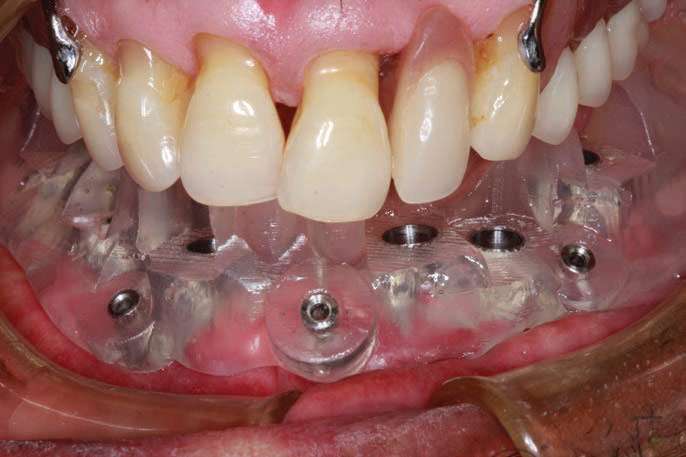

The surgical guide was fabricated per prescription by 3DDX and, after a fine-tuning session, it was returned to be tried in to confirm accuracy (Figure 6a). A guided surgical kit (3DDX Universal guided kit) was used with keys to sequentially enlarge the osteotomies (Figure 6b), and the final drills from the BioHorizons kit were used to finalize the osteotomy prior to implant placement.

BioHorizons implants were selected in order to increase bone-implant contact, as the threads are designed to optimize bone contact as well as utilize Laser-Lok technology (BioHorizons) to hold the hemidesmosomes of the tissue so that the tissues would be less friable and provide for better tissue dynamics. Upon implant placement, a Piezo surgical device (PIEZOSURGERY by Mectron) was used to remove sharp lips of bone as the implants were countersunk by design. The PIEZOSURGERY by Mectron works by using micro-vibrations to cut bone while minimizing soft-tissue trauma. The device and its internal irrigation provides an almost blood-free foundation while cleaning around the implants and removing unwanted tissues. The cutting is micrometric, and the micro-vibrations not only cut bone but help collect bone particles to be used in the defects around the implants so the autogenous shavings can be placed adjacent to the exposed threads or fenestrations[14] (Figure 7).

The BioHorizons implants were placed with a good A-P spread, and the bone in the anterior mandible was left in case it was needed at the uncovery appointment (Figure 8). At the uncovery visit, the LightScalpel laser was used to perform a trephine of the posterior implants by placing the surgical guide, marking the osteotomy sites with a Dr. Thompson’s marking stick, and (using a super-pulsed 2W setting) to gently remove the cuff of tissue over the implants (Figure 9). In the anterior mandible, a full-thickness flap was done, and the remaining bone was removed with the PIEZOSURGERY device (Figure 10). The peri-mucosal healing abutments were placed, and a soft-tissue conditioner was placed in the lower denture (Figure 11). After one month of healing, the patient was ready for impressions (Figure 12).